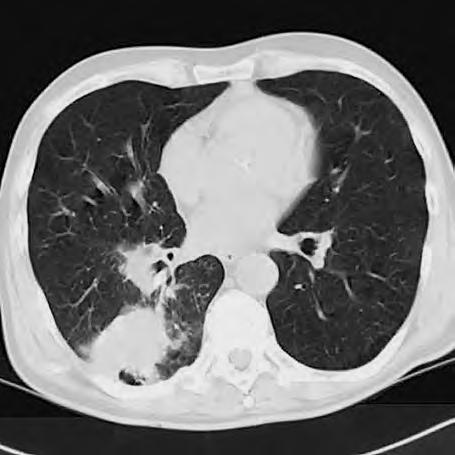

Diferenciální diagnóza

Expanzivní ložisko vCNS může být někdy způsobeno benigním patologickým procesem (abscesem, kavernomem, meningeomem), ale může jít také ometastázu známého nebo doposud ukrytého tumoru, viz obr. 1.4 a1.5. Do mozku často metastazují následující tumory: bronchogenní karcinom, obzvláště jeho malobuněčná varianta, karcinomy prsu aledvin. V80 %případů jsou tyto metastázy uloženy supratentoriálně.

Obr. 1.4 Miliární metastázy mozku bronchogenního karcinomu s okluzí aquaeduktu a hydrocefalem. MR zobrazení v koronárním řezu v T1 váženém čase po aplikaci kontrastní látky i.v. Bílá šipka ukazuje v tektu umístěnou metastázu blokující svou expanzí aquaedukt.

Metastázy mohou vCNS vytvořit jak solitární, tak ivícečetná ložiska, mohou však také infiltrovat meningy (bronchogenní karcinom, karcinomy prsu ižaludku).